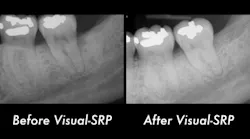

The patient returned after two weeks for a postoperative check of No. 31 and had a maintenance visit at three months post-op. At the three-month mark, the Visual-SRP area was evaluated for results. The pocket depth had resolved to 4 mm without signs of inflammation. A periapical radiograph of the area suggested bone remineralization in the site of No. 18 distal (figure 3). No. 31 was required to heal for six months and was not assessed until that time. At the six-month mark, the patient returned for another maintenance visit. The surgical area was measured, and the pocket depth had resolved to 4 mm without signs of inflammation. The periapical radiograph of No. 31 distal revealed the vertical defect was repaired, and new bone formation was evident (figure 4).

Figure 3: Periapical radiograph of No. 18 distal suggests bone remineralization, three months after nonsurgical treatment with Visual-SRP

Figure 4: Periapical radiograph of No. 31 distal shows a repaired vertical defect and new bone formation, six months after treatment with periodontal pocket reduction surgery and bone regenerative materials

This case illustrates the potential for Visual-SRP to yield results typically gained with a surgical approach. The healing time for Visual-SRP is far shorter than the healing time for surgery. This improves the oral health of the patient and, with remineralized bone, reduces the risk of recurring periodontal inflammation.